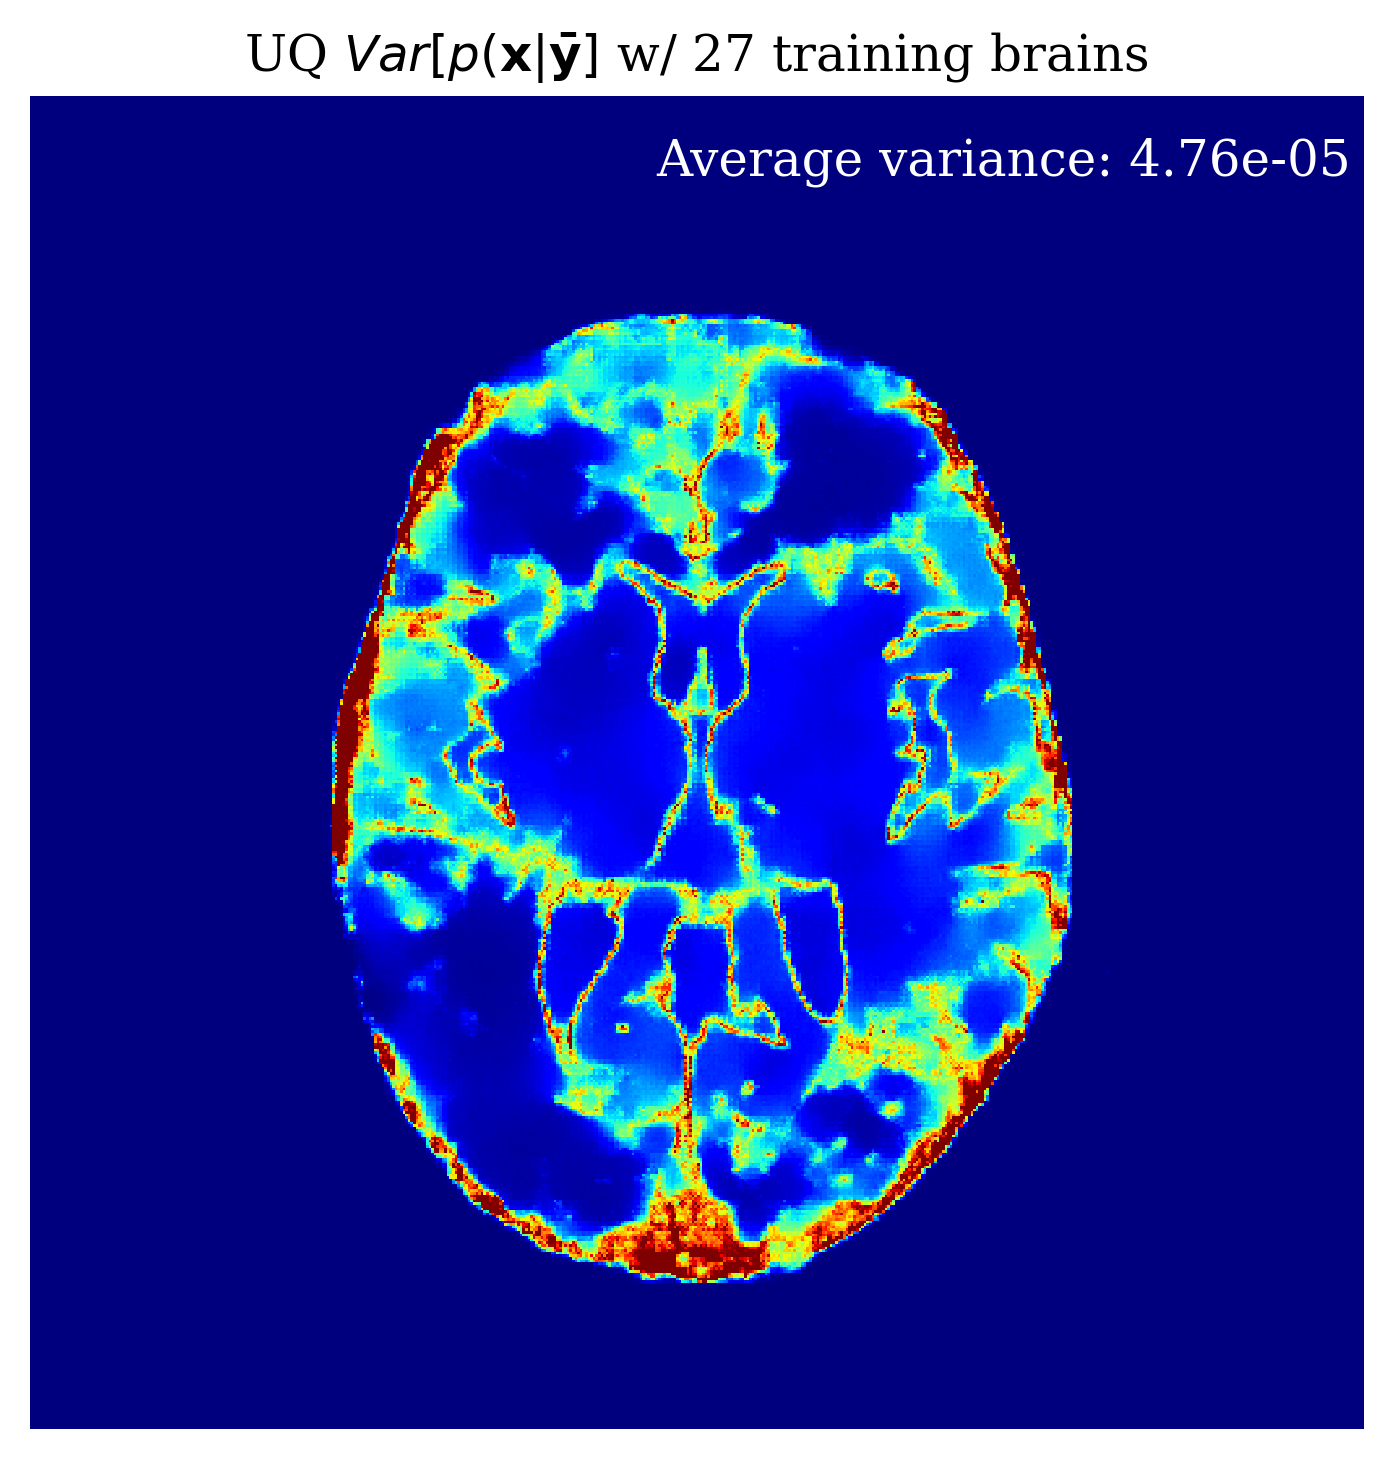

Since our method is Bayesian, its UQ results depend on how well it has learned the prior from training examples. In the case of conditional normalizing flows the prior is not explicitly accessible from the network since the network directly learns to sample the conditional distribution. Nonetheless, we would like to gain intuition on the effect of more training samples on the methods performance. In \figurereffig:trainingsize, we demonstrate the effect of increasing the training dataset size, on the posterior mean quality and on the UQ map that is produced. We observe from \figurereffig:trainingsize that as training samples increase, the posterior mean gets closer to the ground truth and that the UQ map becomes more contracted. These observations are similar to what happens when we increase the amount of observed data as explained in \sectionrefsec:uncertainty.

\subfigure

\subfigureUQ

\subfigureError

|

\subfigureGround truth